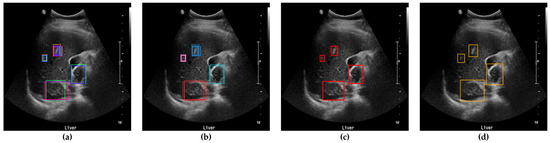

After clustering and outlier reduction, SM-WBF was applied to generate a single representative bounding box for each cluster. SM-WBF calculated weights for each bounding box by normalizing the mAP@0.5 values of the ten networks using the SoftMax function. These SoftMax weights were then used to combine the center coordinates and dimensions of the bounding boxes within each cluster through a weighted average approach. This method ensured that bounding boxes from higher-performing networks contributed more significantly to the result. Details of this process are illustrated in Figure 7.

Figure 7. (a) An image with all bounding boxes detected by YOLOv8 overlaid, and the results of bounding box optimization through (b) clustering, (c) SM-WBF, and (d) padding. (e) Ground truth bounding box.